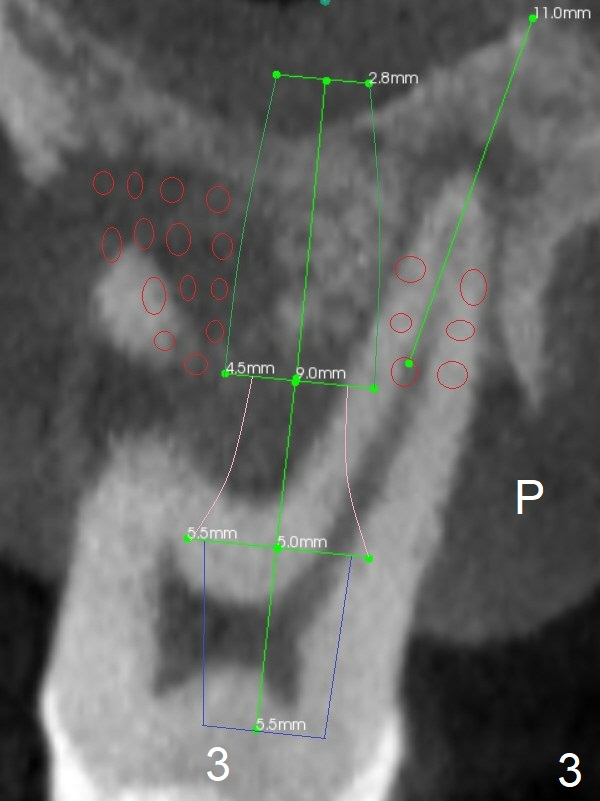

A 36-year-old man with chronic periodontitis will return for #3 and 5 extraction and FPD (Fig.1,2). The initial depth of the septum of #3 will be <8.5 mm (Fig.3). The septum seems narrow; bone expansion will be done with DIO bone expander kit. The osteotomy at #5 will be in the palatal socket (Fig.4 P). Take photos for Lower Anterior provisional.